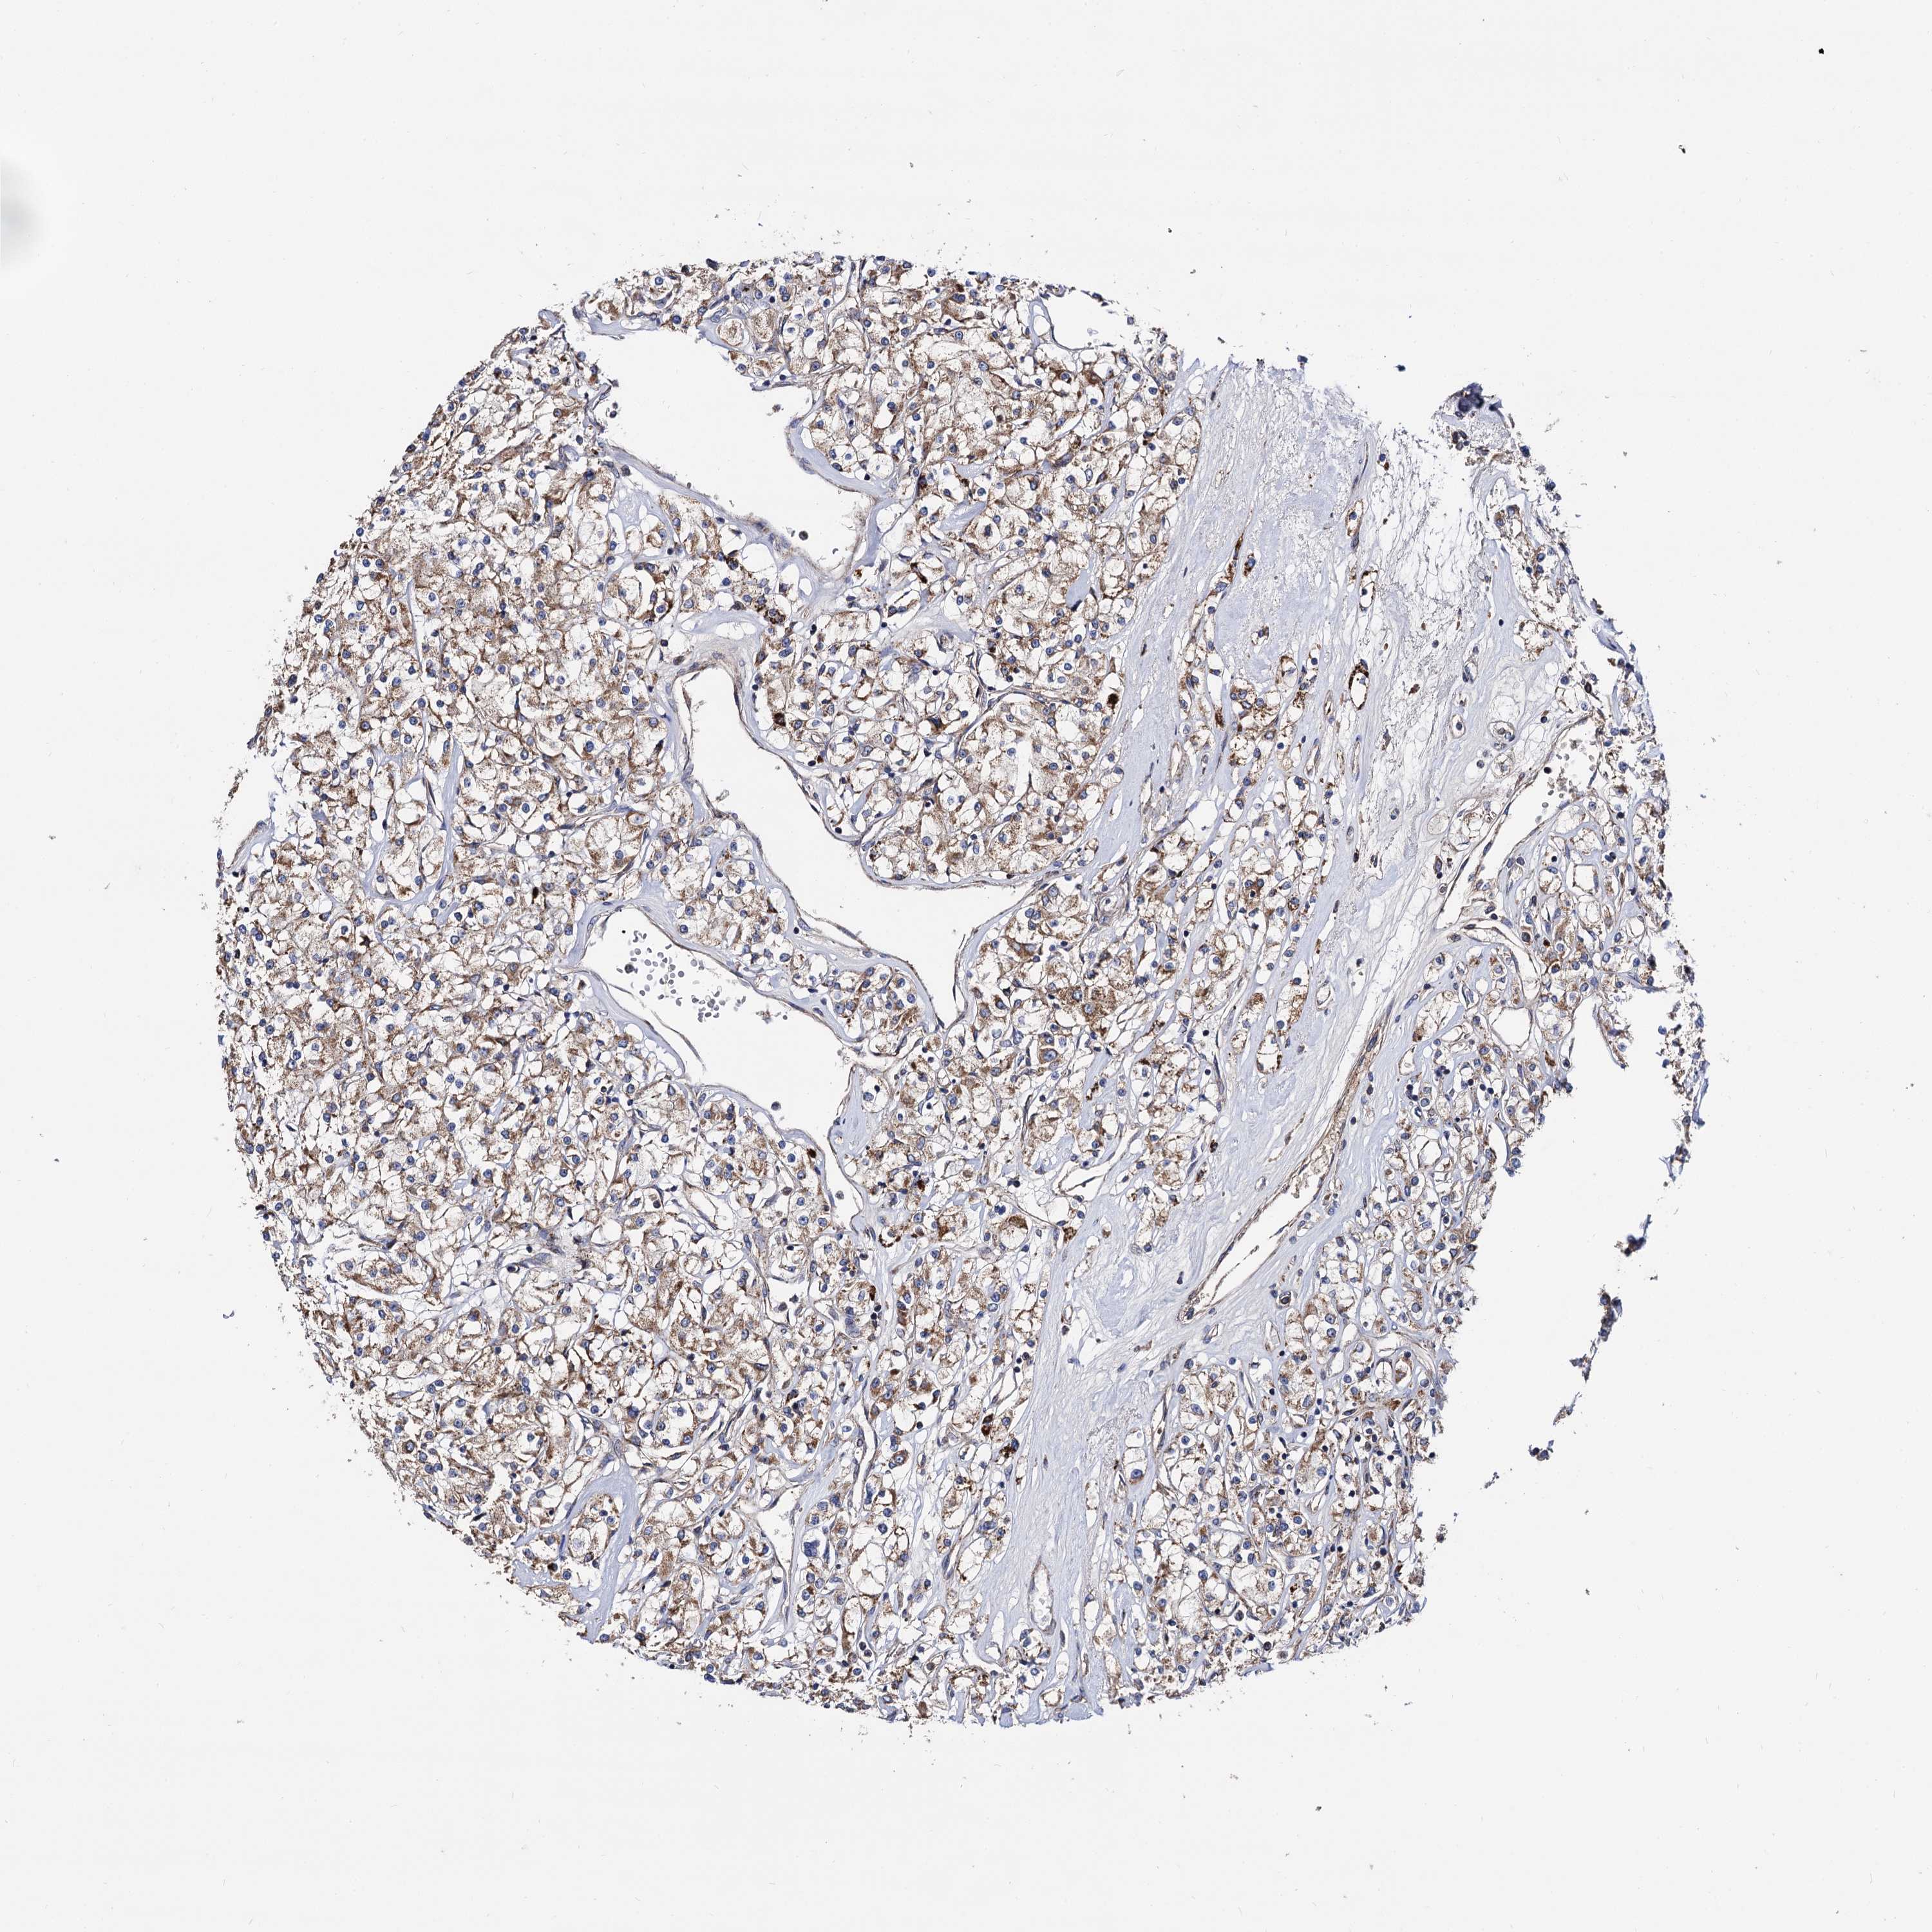

KIDNEY RENAL CLEAR CELL CARCINOMA (VALIDATION) - Interactive survival scatter ploti

The Survival Scatter plot shows the clinical status (i.e. dead or alive) for all individuals in the patient cohort, based on the same data that underlies the corresponding Kaplan-Meier plots. Patients that are alive at last time for follow-up are shown in blue and patients who have died during the study are shown in red.

The x-axis shows the expression levels (FPKM) of the investigated gene in the tumor tissue at the time of diagnosis. The y-axis shows the follow-up time after diagnosis (years). Both axes are complimented with kernel density curves demonstrating the data density over the axes. The top density plot shows the expression levels (FPKM) distribution among dead (red) and alive patients (blue). The right density plot shows the data density of the survived years of dead patients with high and low expression levels respectively, stratified using the cutoff indicated by the vertical dashed line through the Survival Scatter plot. This cutoff is automatically defined based on the FPKM cutoff that minimizes the p-score. The cutoff can be changed by dragging the vertical line or by entering a cutoff value in the square labeled "Current cut-off".

Under the Survival Scatter plot the p-score landscape (black curve; left axis) is shown together with dead median separation (red curve; right axis). Dead median separation is the difference in median mRNA expression between patients who have died with high and low expression, respectively. It is calculated as follows: median FPKM expression of dead patients with high expression - median FPKM expression of dead patients with low expression. This is intended to aid the user in visually exploring custom cutoffs and the associated p-scores and dead median separation.

Individual patient data is displayed and can be filtered by clicking on one or more of the category buttons on the top of the page. Categories describing expression level and patient information include: high, low, alive, dead, female, male and tumor stages. The scale of the x-axis can be toggled between linear and log-scale by clicking on the "x log" button. Mouse-over function shows TCGA ID, patient information and mRNA expression (FPKM) for each patient.

& Survival analysisi

Kaplan-Meier plots summarize results from analysis of correlation between mRNA expression level and patient survival. Patients were divided based on level of expression into one of the two groups "low" (under cut off) or "high" (over cut off). X-axis shows time for survival (years) and y-axis shows the probability of survival, where 1.0 corresponds to 100 percent.

IQCH is not prognostic in Kidney Renal Clear Cell Carcinoma (validation)

Best expression cut offi

Based on the FPKM value of each gene, patients were classified into two groups and association between prognosis (survival) and gene expression (FPKM) was examined. The best expression cut-off refers the FPKM value that yields maximal difference with regard to survival between the two groups at the lowest log-rank P-value. Best expression cut-off was selected based on survival analysis .

When clicking on this number, the vertical dashed line indicating cut-off, the interactive survival plot, and the Kaplan-Meier curve will be adjusted to show results based on the best expression cut-off.

: 0.77

P scorei

Log-rank P value for Kaplan-Meier plot showing results from analysis of correlation between mRNA expression level and patient survival.

N/A

TCGA RNA samplesi

RNA-seq data is reported as average FPKM (number Fragments Per Kilobase of exon per Million reads), generated by the The Cancer Genome Atlas (TCGA) .

Normal distribution across the dataset is visualized with box plots, shown as median and 25th and 75th percentiles. Points are displayed as outliers if they are above or below 1.5 times the interquartile range. FPKM values of the individual samples are presented next to the box plot.

Average pTPM 1.4

Number of samples 100